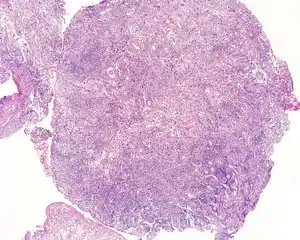

| An intermediate magnification of a H&E stained biopsy from an otic polyp. | |

By microscopic exam, the polypoid appearance is maintained, showing a granulation-type tissue reaction with edematous stroma and a rich investment by capillaries. The surface of the polyp is covered by stratified squamous epithelium with a prominent granular cell layer. The tissue is filled with lymphocytes, plasma cells, mast cells, histiocytes, and eosinophils. It is not uncommon to see plasma cells with Russell bodies and Mott cell formation. Depending on length of symptoms, multinucleated giant cells and calcifications may be seen. Other disorders may be concurrently present, especially since this is a post infectious/inflammatory disorder, and these include a cholesterol granuloma, "tunnel clusters" (glandular epithelial inclusions below the surface epithelium), and cholesteatoma.[3][4][5]